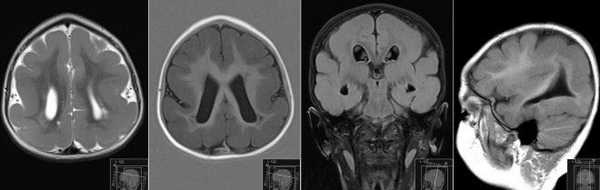

Бипариетальный размер головки плода измеряли при визуализации М-эхо на уровне III желудочка мозга, на одинаковом расстоянии от теменных костей, при получении изображения полости прозрачной перегородки и четверохолмия. Измерение производили от наружного до внутреннего контура теменных костей. Определение лобно-затылочного размера осуществляли между наиболее удаленными точками наружных контуров лобной и затылочной костей черепа плода.

Размер представляет собой расстояние между теменными костями в поперечной плоскости. Для того, чтобы получить такое изображение, специалисту ультразвуковой диагностики нужно поместить датчик сканера таким образом, чтобы головка была сверху.

У малышей, которые еще только растут в уютном мамином животике, голова по форме совсем не такая, как у нас с вами — она округлая, овальная. А потому одно лишь расстояние между теменными костями не даст точного представления о темпах роста головы малыша. БПР всегда «соседствует» с другим размером — ЛЗР (это лобно-затылочный размер, который представляет собой расстояние между лобной и теменной костью). Два отрезка (ЛЗР и БПР) друг другу перпендикулярны. Бипариентальный размер указывает на ширину головы малыша.